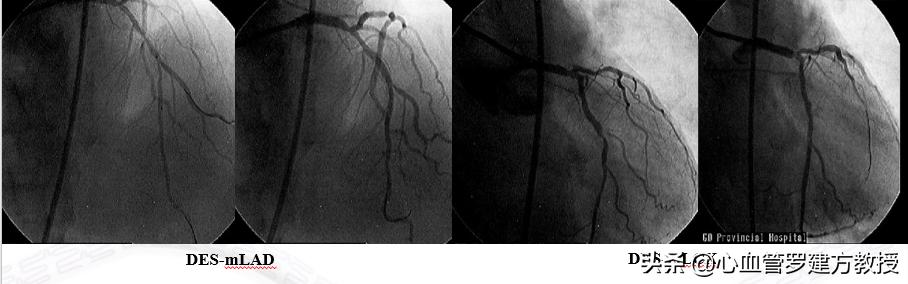

冠脉造影

冠脉造影结果发现,左主干末段狭窄60%-70%,前降支开口狭窄70%,中段狭窄80%,旋支开口狭窄60%-70%,中段长病变,最重狭窄70%,右冠中段狭窄30%,远段狭窄50%,这个检查结果也说明我们的判断是正确的。

我很清楚地记得,这个患者是2006年12月14日做的PCI,分别干预前降支和回旋支后,采用T支架术在左主干植入了1枚药物支架。